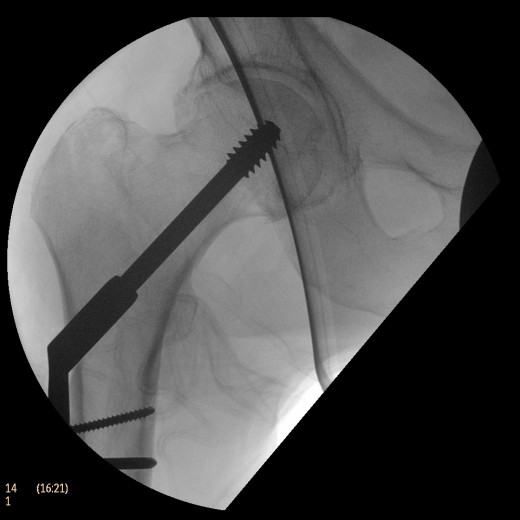

Система Philips BV Endura, рассчитанная на выполнение рутинных задач, расширяет возможности процедур на сосудах. Компактный размер 9-дюймового усилителя изображения обеспечивает маневренность для ортопедии и травматологии, а 12-дюймовый обеспечивает превосходный охват для выполнения сосудистых процедур, урологии и общей хирургии. Кроме того, мы увеличили угол поворота C-дуги до 135°, чтобы дать возможность получения проекций, необходимых для большинства процедур на сосудах.

Полностью цифровая цепь формирования изображений с матрицей 1024х1024 использует передовые средства шумоподавления и двумерного подчеркивания контуров для создания изображений с высоким качеством.